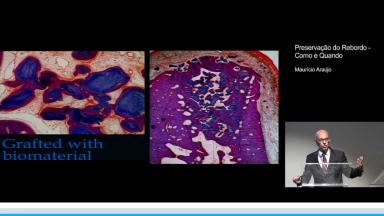

O objetivo da aula é saber como e quando preservar o processo alveolar que contenha volume suficiente para procedimentos reabilitadores. Baseado em trabalhos de pesquisa padronizados, dicas científicas e um ótimo recurso visual, preservar o processo alveolar se torna uma ótima solução. Com técnicas de exodontia minimamente invasivas e menos traumáticas; a exodontia dentária passa a ser um passo fundamental no processo de preservação alveolar. Atenção é dada a ação de biomateriais não reabsorvíveis, colocados no sítio de extração impedindo a ação osteoclástica. A aula demonstra além da técnica de exodontia, enxertia e seus fundamentos na preservação do processo alveolar, como também comparação entre resultados de enxertia com osso autógeno e com biomateriais não reabsorvíveis.

- Relacionar técnicas de preservação alveolar com osso autógeno e biomateriais não reabsorvíveis